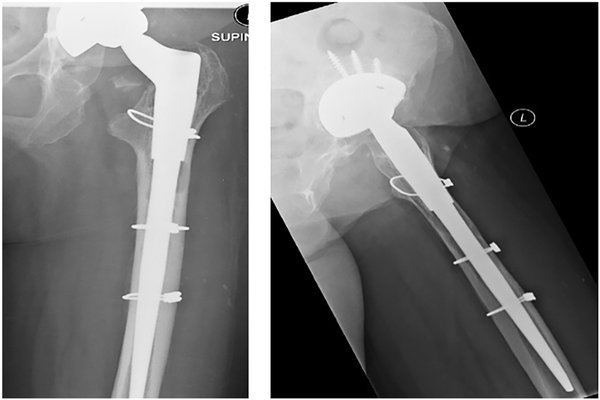

The canal was prepared by successive reaming for the long stem prosthesis, aiming to bypass the distal extent of the cortical window by at least twice the femoral diameter as recommended by Klein and Rubash. In aseptic cases, a modular, distal-fit uncemented ZMR stem was used (Zimmer) (Figure 6.) On occasion a cerclage wire would be applied to the proximal femur to prevent propagation of a fissure to the window when it became apparent whilst inserting the revision femoral stem (Figure 8.) In septic cases undergoing first-stage revision, either a Tecres Spacer G or a Biomet StageOne Select spacer was implanted, again bypassing the femoral window by at least twice the femoral diameter. The cortical window was replaced and secured with further Dall-Miles cables. In non-infected cases, cancellous bone graft from the femoral canal reamings was placed around the corticotomy.

All 22 cases involved revision of a cemented femoral component. 16 single-stage revisions were performed for aseptic loosening, 10 of which included revision of both femoral and acetabular components, and 6 the femoral component only. 6 patients underwent first stage revision for deep infection (Table 1.) Of the 16 single-stage revisions performed, Zimmer ZMR taper stems (185 mm distal stem length) were implanted in all cases. Of the 6 first-stage revisions performed for infection, long cement spacers were implanted in all cases. 5 of these 6 patients went on to second-stage revision using the Zimmer ZMR (185 mm length) stem. In 2 patients the ZMR prosthesis subsided 1 cm.

Review of radiographs revealed full integration of the cortical window in 21 cases. The earliest time to integration was 4 months. The following plain radiographs of a patient revised for aseptic loosening at day-1 and at 12 months post-surgery, respectively (Figures 7 and 8).

Figure 8

AP and lateral radiographs day-1 post-surgery. The femoral window cannot be appreciated on the AP view as it overlies the femoral component The superior and inferior transverse limbs of the cortical window are visible on the lateral view. Note proximal cerclage wire applied to prevent fracture propagating to the window whilst inserting the revision femoral stem.

Radiographs confirmed 2 cases of femoral stem subsidence of 1 cm. Both stems stabilised subsequently. CT scans were performed between 5 months and 9 years postoperatively (mean 30 months) (Table 1). The mean rectangular-shaped window size was 8 × 1.5 cm, with width variation of 1–2 cm. Average overall integration score was 0.84 (range scores 0.44–1). 3 patients demonstrated complete union of the cortical window. Using interclass correlation coefficient, inter-observer agreement was 0.86, and mean intra-observer agreement was 0.88 (0.79, 0.92, 0.92) for the first 16 cases. Values >0.8 are considered to show very good agreement, and >0.9 show excellent agreement.

There were no cases of postoperative periprosthetic fractures in this series, however, minor proximal intraoperative fractures did appear from time to time whilst inserting the revision femoral stem. Propagation of the fissure to the window was prevented when a cerclage wire was applied proximally (Figure 8). As described by other authors, it is important to use a revision stem that bypasses the cortical window as reported by Klein and Rubash.